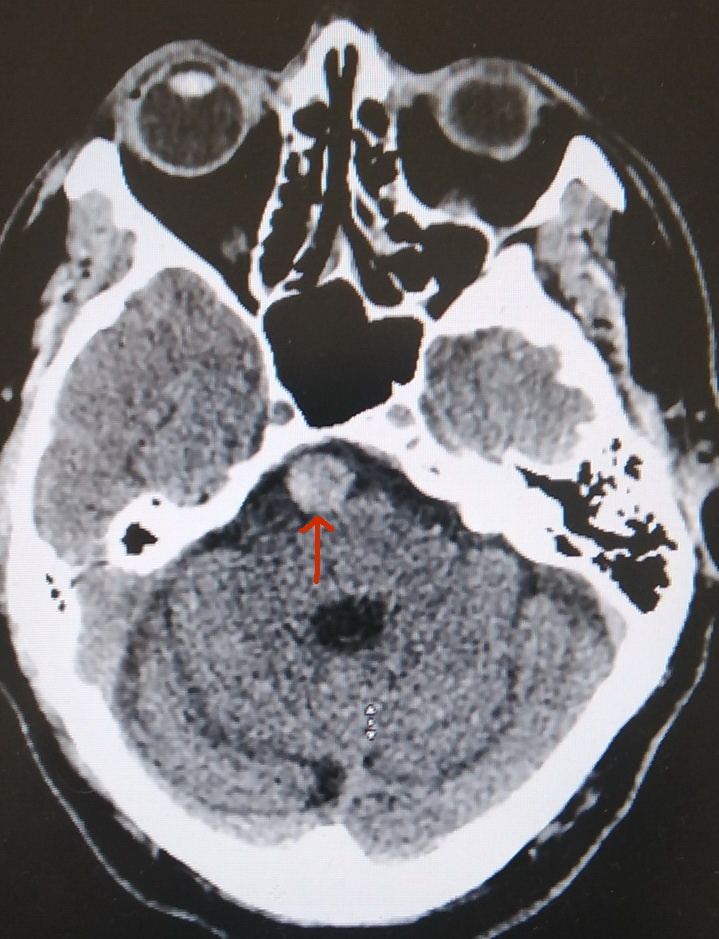

Этот "шарик" и есть аневризма.

КТ выявила аневризму основной артерии головного мозга (arteria basilaris). К счастью, аневризма цела. При введении контрастного вещества признаков её разрыва не выявлено, но, безусловно, находка серьёзная. Разрыв таких аневризм чрезвычайно опасен, и обычно приводит к непоправимым последствиям.